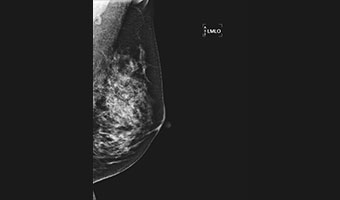

全乳覆盖高效检查

低剂量高清图像

微小病灶,清晰呈现

24×30cm大面积成像,

放大摄影功能,微小病灶无处遁形

低剂量高清晰兼顾

进口钼靶球管 X射线更适合乳腺检查 管球寿命更高 钼铑双滤过,根据乳房致密度自动智选